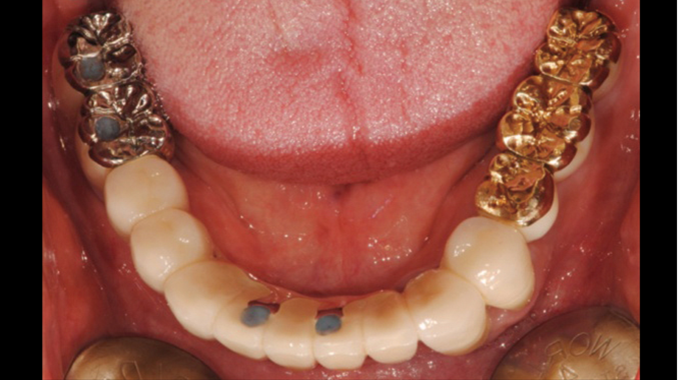

Clinical case: Full-mouth implants for mandibular & maxilla - restored using mixed prostheses

- Courtesy of Dr. Hyun Jun Kim, Korea -

Keywords

AnyRidge, full-mouth implants, mandibular, maxilla, edentulous, full mouth rehabilitation, Octa abutment, long-term clinical case, biological stability, Dr. Hyung Jun Kim

Products:

AnyRidge implant system